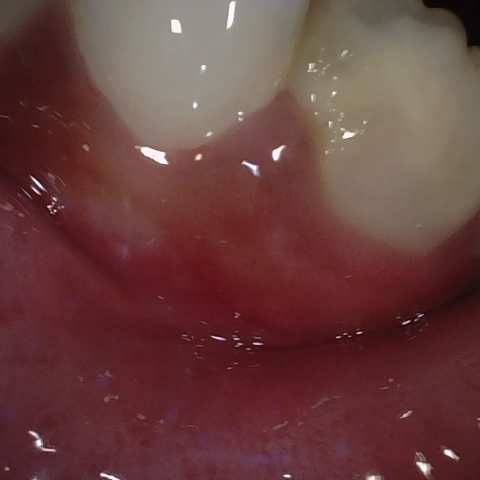

Annotated as "Good"